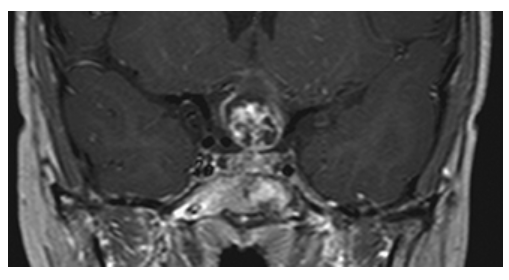

Ependymoma. Axial NECT shows a large mass with calcifications arising from the fourth ventricle and extending posteriorly. There is also hydrocephalus due to obstruction of cerebral spinal fluid (CSF) flow by the mass.

Ependymoma. Sagittal T2W image shows the large irregular mass arising from the fourth ventricle, compressing the cerebellum and herniating down the spinal canal. There is also severe hydrocephalus due to obstruction of CSF flow.

Ependymoma. Postcontrast T1W sagittal image shows irregular enhancement of the mass.